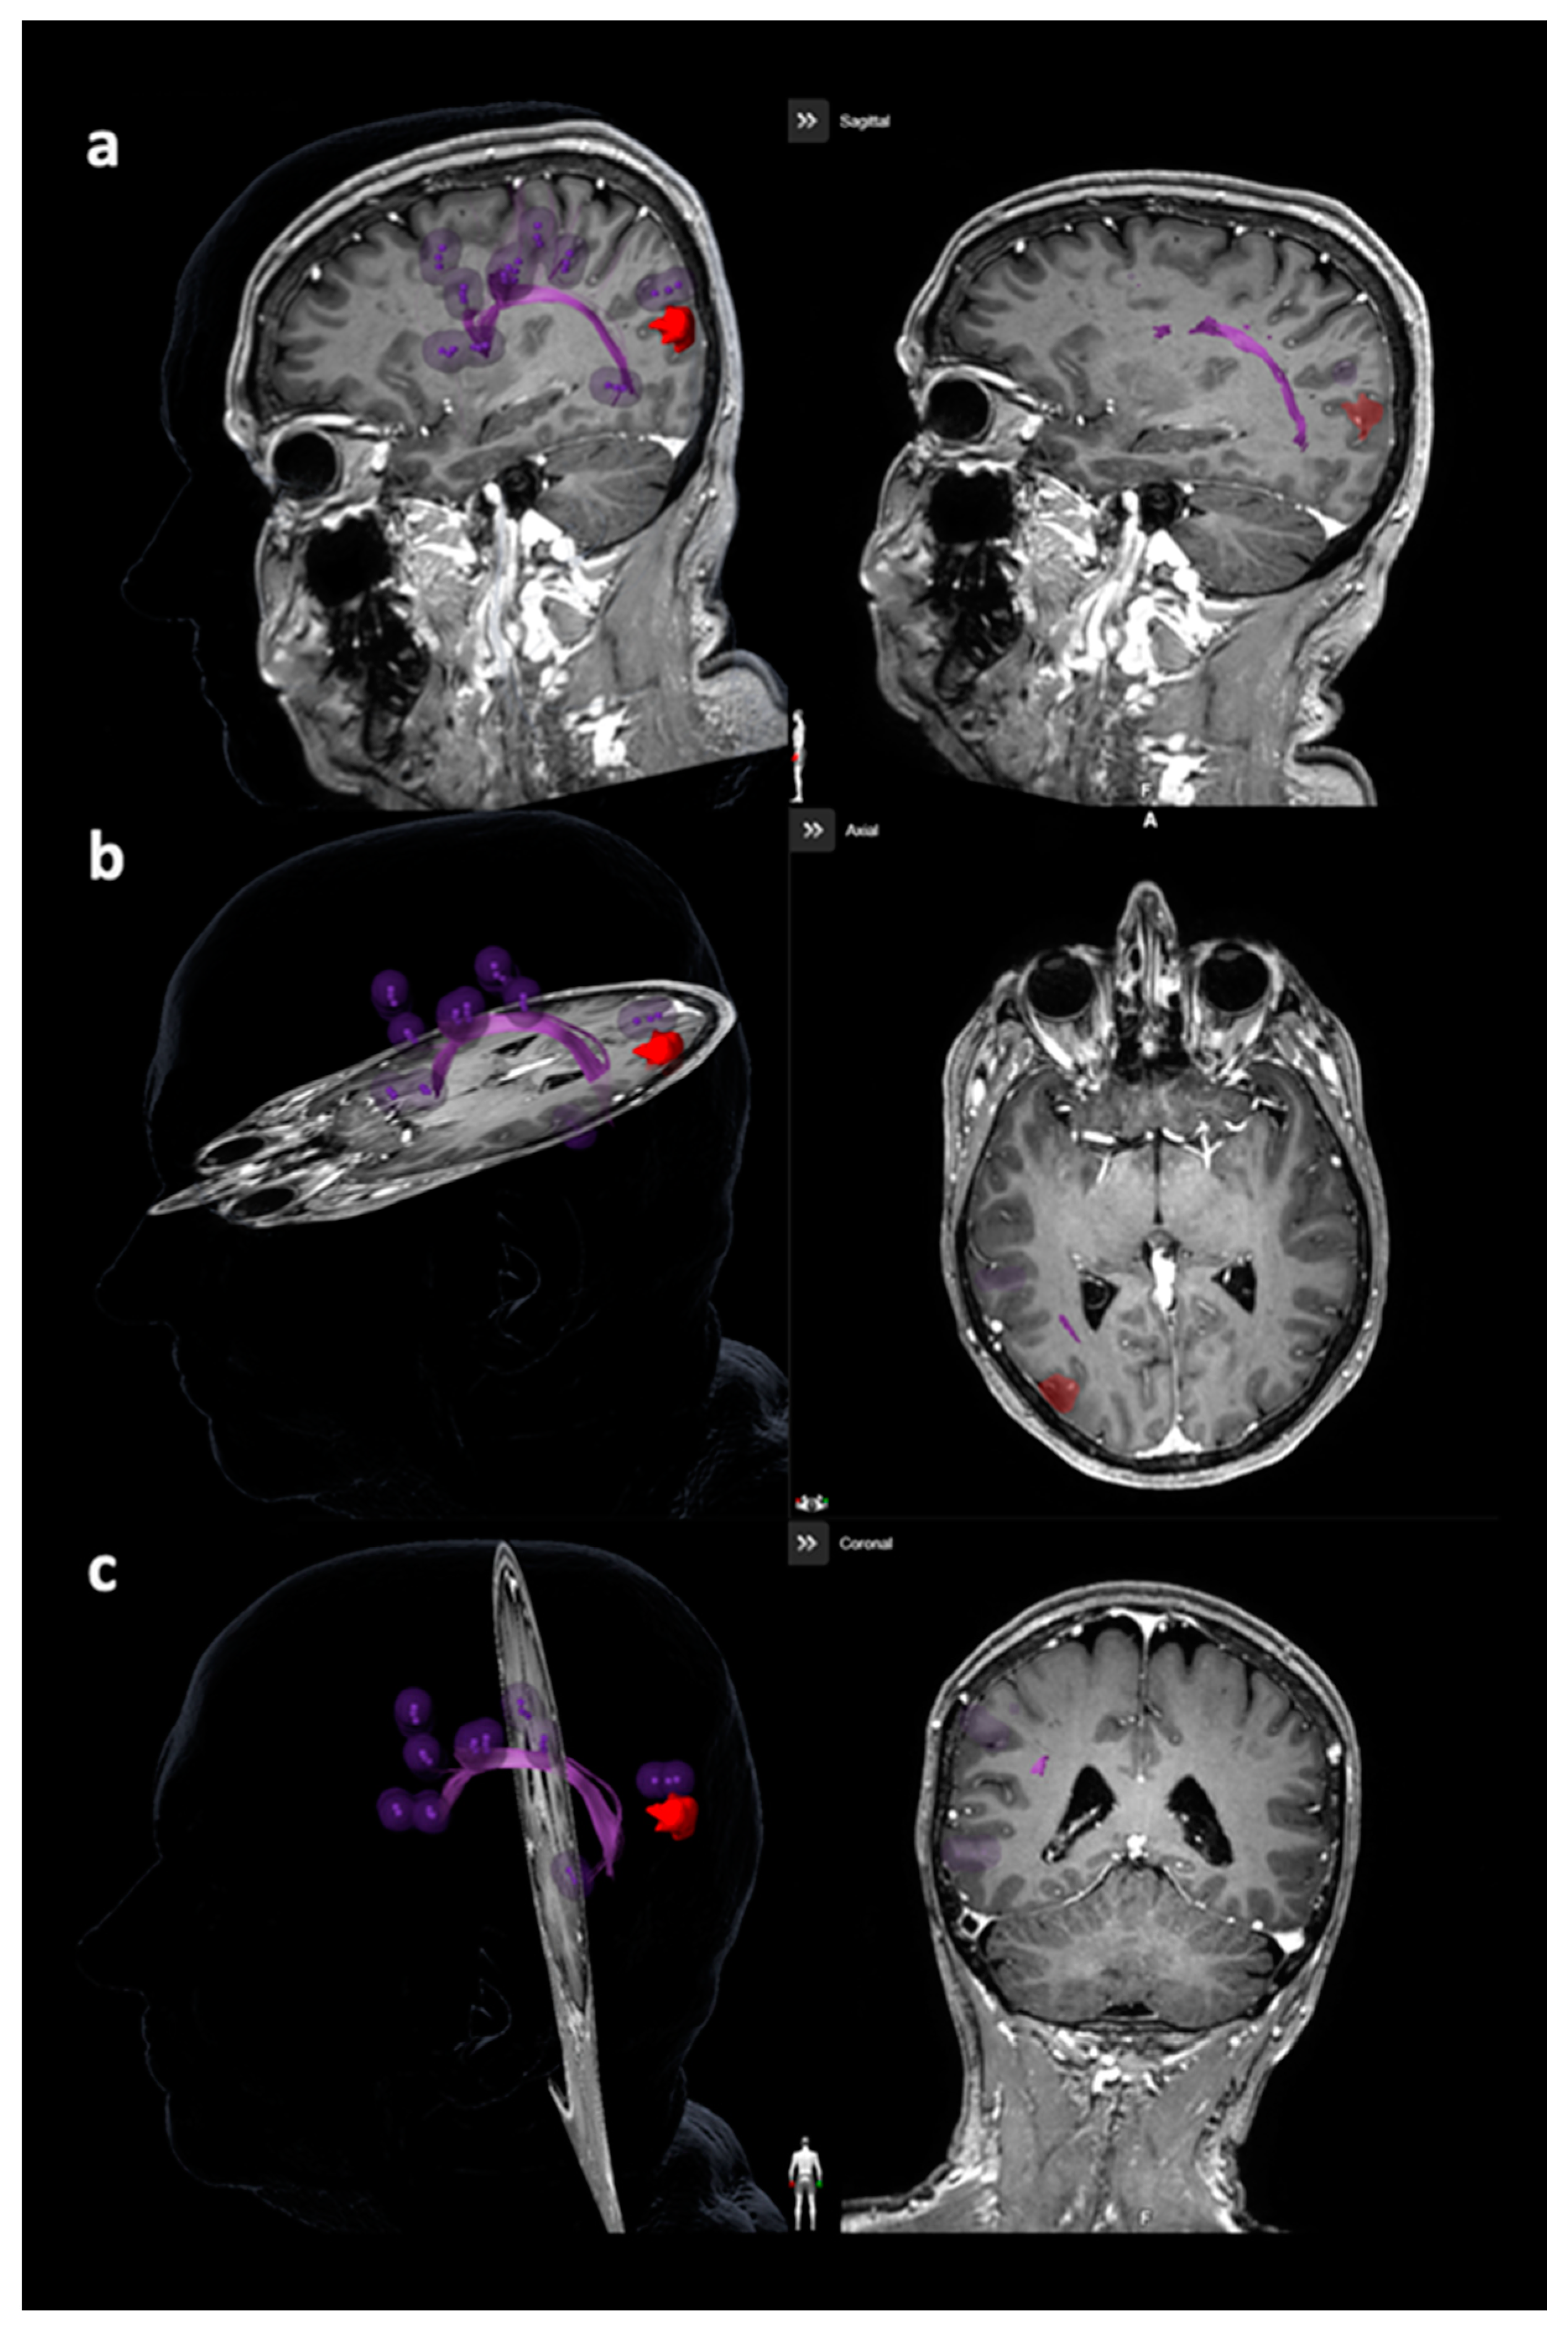

Figure 2. Visualization of the arcuate fascicle (AF). This figure depicts the AF in purple considering all planes ((a): sagittal plane, (b): axial plane, (c): coronal plane), with the reconstruction being purely based on diffusion tensor imaging fiber tracking (DTI FT) using the language map derived from navigated transcranial magnetic stimulation (nTMS). The language map is represented by purple spots, while the tumor volume is enclosed in red.

Tractography of the AF or other closest language-related tracts considering the superior longitudinal fascicle (SLF), inferior longitudinal fascicle (ILF), uncinate fascicle (UC), and frontooccipital fascicle (FoF) was performed with language-positive nTMS points with a rim of 5 mm as the only ROI (Figure 2 and Figure 3) [23,27,30]. Similar to nTMS-based DTI FT of the CST, a minimum FL of 100 mm was combined with 25%, 50%, and 75% FAT [23,27,30]. The LTD for the AF or other closest language-related tract (either SLF, ILF, UC, or FoF) was defined in FLAIR and/or contrast-enhanced 3D gradient echo sequences by linearly measuring the minimum distance between the border of the solid tumor mass and the closest fibers of the AF or other closest language-related tracts (Figure 4) [27].